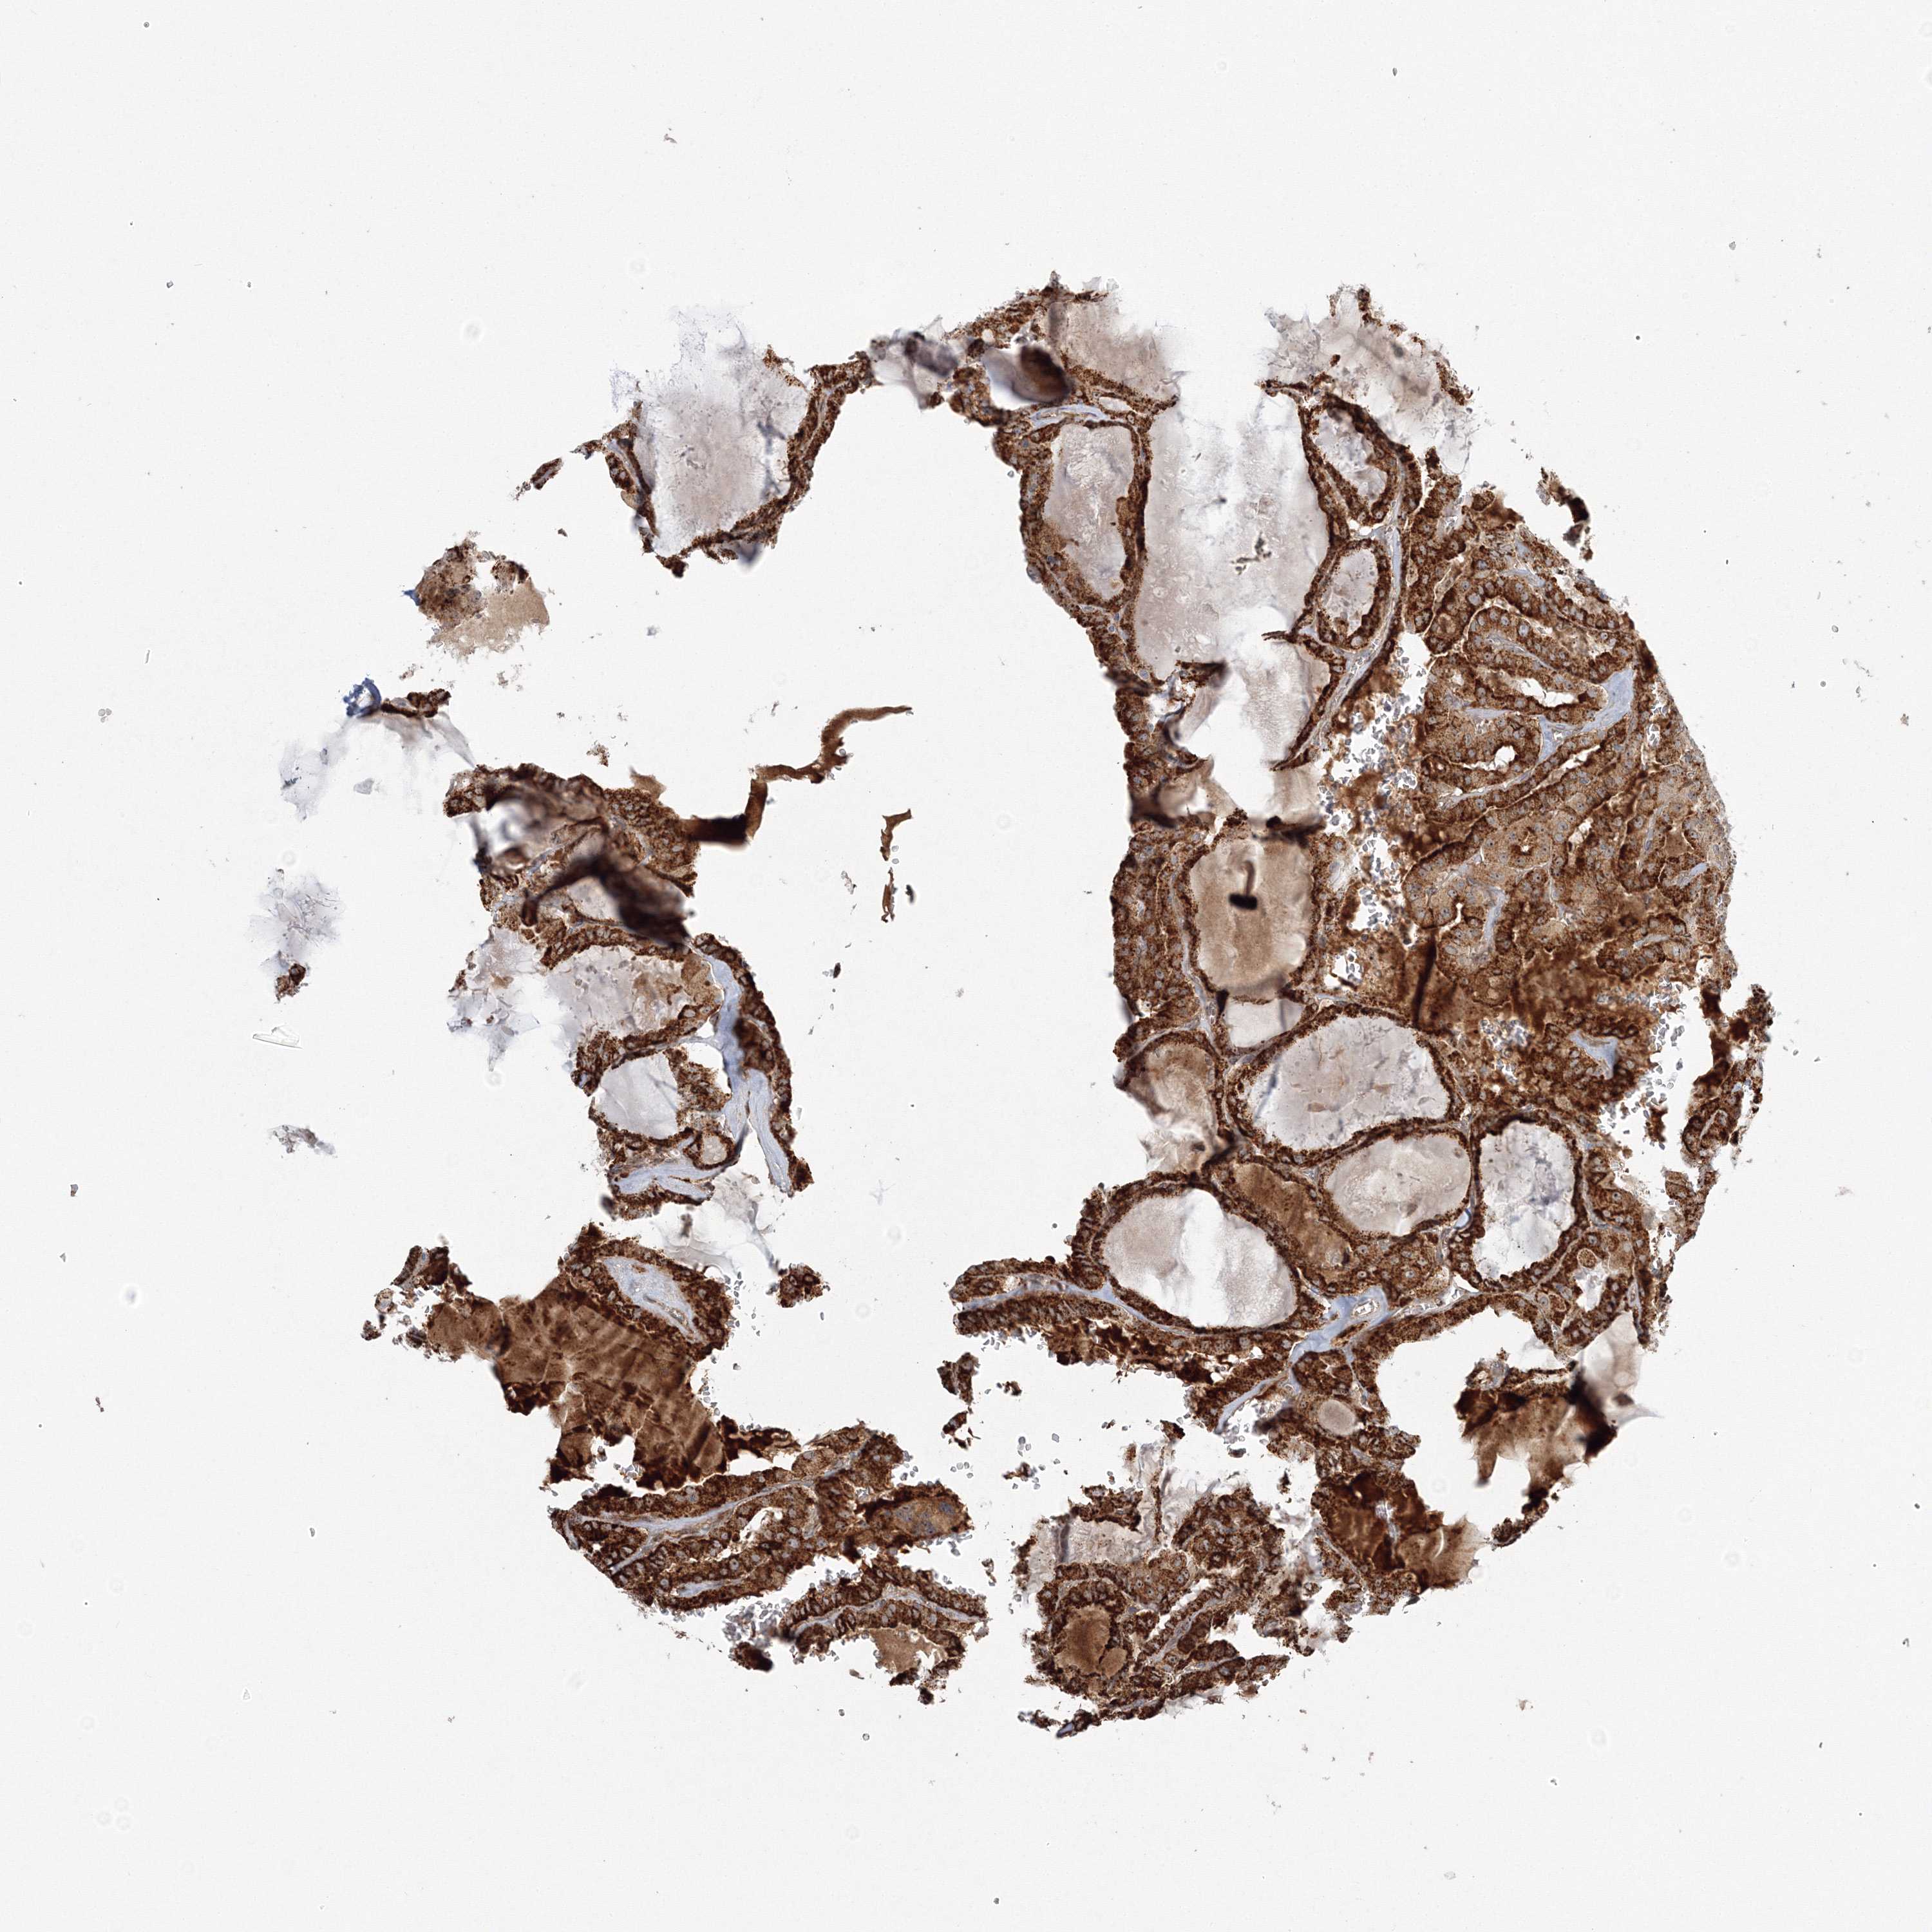

THYROID CANCER - Protein expressioni

A mouse-over function shows sample information and annotation data. Click on an image to view it in a full screen mode. Samples can be filtered based on level of antibody staining by selecting one or several of the following categories: high, medium, low and not detected. The assay and annotation is described here.

Note that samples used for immunohistochemistry by the Human Protein Atlas do not correspond to samples in the TCGA dataset.

Antibody stainingi

Antibody staining in the annotated cell types in the current human tissue is reported as not detected, low, medium, or high, based on conventional immunohistochemistry profiling in selected tissues. This score is based on the combination of the staining intensity and fraction of stained cells.

Each image is clickable and will lead to virtual microscopy that enables deeper exploration of all samples and also displays staining intensity scores, fraction scores and subcellular localization as well as patient and tissue information for each sample.

Antibody HPA036295

Antibody HPA036296

Staining

High

Medium

Low

Not detected

Intensity

Strong

Moderate

Weak

Negative

Quantity

>75%

75%-25%

<25%

None

Location

Nuclear

Cytoplasmic/membranous

Cytoplasmic/membranous,nuclear

Papillary adenocarcinoma, NOS

Follicular adenoma carcinoma, NOS